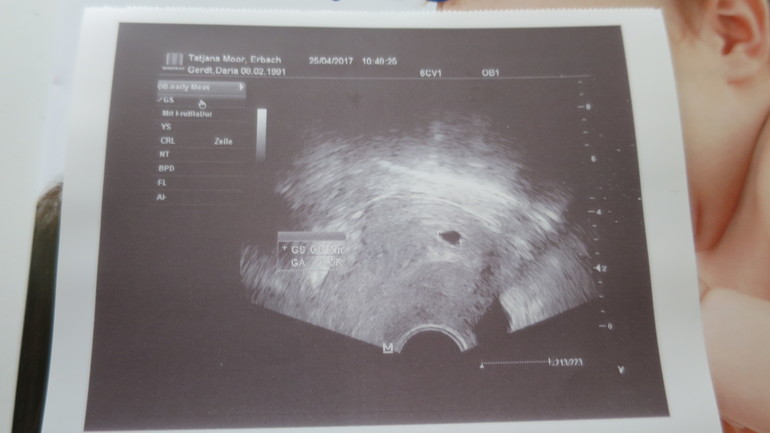

Первое УЗИ

УЗИ, КТГ, доплерСегодня сходила на узи, Ура....ПЯ там где надо, сердцебиение еще не, рано....пойдем проверять 11 мая. На УЗИ пошла из за не понятного жжения. Вторая Б как и первая началась с молочницы. Наше первое фото))))